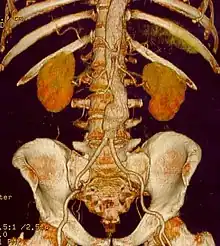

Abdominal aortic aneurysm

Abdominal aortic aneurysms (AAAs) are more common than their thoracic counterpart. One reason for this is that elastin, the principal load-bearing protein present in the wall of the aorta, is reduced in the abdominal aorta as compared to the thoracic aorta. Another is that the abdominal aorta does not possess vasa vasorum, the nutrient-supplying blood vessels within the wall of the aorta. Most AAA are true aneurysms that involve all three layers (tunica intima, tunica media and tunica adventitia). The prevalence of AAAs increases with age, with an average age of 65–70 at the time of diagnosis. AAAs have been attributed to atherosclerosis, though other factors are involved in their formation.[8] Risk factors for AAA include the male gender, aging, a history of smoking, hypercholesterolemia, and hypertension.[4][8][11] Reviews reported estimates for prevalence rates of AAA were 0.9-9% in men and 1–2% in women, where, generally, the incidence of AAA is four times greater in men compared to women at the same age.[4][8]

The risk of rupture of an AAA is related to its diameter; once the aneurysm reaches about 5 cm, the yearly risk of rupture may exceed the risks of surgical repair for an average-risk patient. Rupture risk is also related to shape; so-called "fusiform" (long) aneurysms are considered less rupture-prone than "saccular" (shorter, bulbous) aneurysms, the latter having more wall tension in a particular location in the aneurysm wall.[12]

Before rupture, an AAA may present as a large, pulsatile mass above the umbilicus. A bruit may be heard from the turbulent flow in the aneurysm. Rupture may be the first sign of AAA. Once an aneurysm has ruptured, it presents with classic symptoms of abdominal pain which is severe, constant, and radiating to the back.[8]

The diagnosis of an abdominal aortic aneurysm can be confirmed by the use of ultrasound. Rupture may be indicated by the presence of free fluid in the abdomen. A contrast-enhanced abdominal CT scan is the best test to diagnose an AAA and guide treatment options.[14]